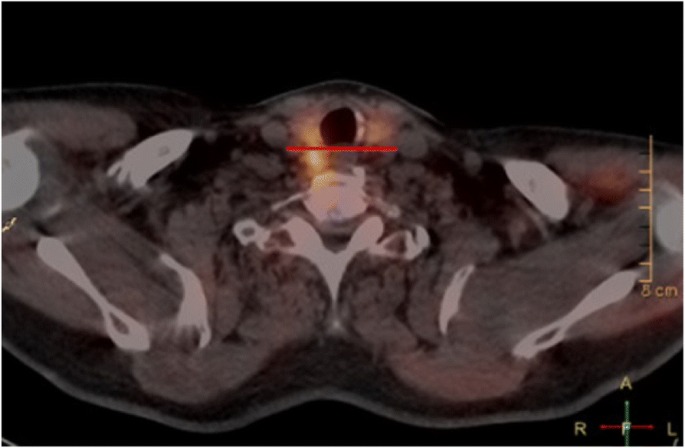

Determining whether a parathyroid adenoma represents an inferior or superior adenoma can be difficult on imaging. This is preoperative localization is, however, paramount to successful excision, as superior and inferior glands are approached differently during surgery. Inaccurate localization seen in some traditional methods can result in more extensive or revision surgery. We have developed a novel method, known as the Harris method, of localizing parathyroid adenoma as inferior or superior based on SPECT/CT imaging. This method is based on the embryological origin and migration pathway of the parathyroid glands, as opposed to the traditional radiological method of their relation to the thyroid gland only. The technique consists of drawing a horizontal (coronal) line on axial cuts of SPECT/CT, bisecting the tracheoesophageal groove at the level of the cricoid cartilage. Adenomas that are anterior to this line on axial cuts are deemed inferior, while adenomas that are posterior to this line are superior. The aim of our study is to determine the validity and accuracy of this novel method for localization of parathyroid adenomas when compared to traditional radiological reporting, against the gold standard of intra-operative localization.

Using SPECT/CT images, two staff Otolaryngologist – Head and Neck Surgeons, a Nuclear Medicine Radiologist, an Otolaryngology – Head and Neck Surgery fellow and resident performed the novel method, blinded to the operative findings, on eligible patients that met the inclusion and exclusion criteria. This novel method consisted of finding the level of the cricoid cartilage on an axial cut of the SPECT/CT and drawing a horizontal line bisecting the tracheoesophageal groove. The participants were then to identify whether the adenoma is anterior or posterior to that line. Data was recorded and participants were given immediate feedback as to their diagnostic accuracy. Participants were given 30 scans in one session to prevent fatigue.

Technological advances have technology has improved accuracy of correct localization of parathyroid adenomas. Preoperatively, it is important to localize these adenomas, as it dictates the surgical approach used to resect the enlarged gland. Of significant clinical importance is the ability to predict the location of the adenoma with respect to the recurrent laryngeal nerve. All superior adenomas (Fig. 3) that would be embryologically and anatomically deep to the recurrent laryngeal nerve require positive identification of the nerve prior to dissection, and resection of, the involved gland. Inferior adenomas are anterior to the recurrent laryngeal nerve and, therefore, dissection on the anterior surface of the gland is safely performed prior to identification of the nerve. Indeed, in some cases the inferior adenoma can be safely excised without identifying the nerve, though in our practice the nerve is identified prior to closure in virtually all cases. Multiple modalities have been used to help achieve localization, however, there is still ambiguity, especially with regards to identifying superior versus inferior gland enlargement.